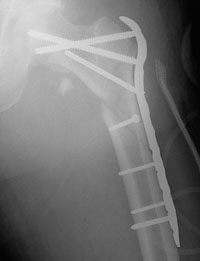

Most intertrochanteric fractures are managed with either a compression hip screw or an intramedullary nail, which also allows for impaction at the fracture site.

The compression hip screw is fixed to the outer side of the bone with bone screws and has a large secondary screw (lag screw) that is placed through the plate into the neck and head of the hip (see compression hip screw figure above). The design of the device allows for impaction and compression at the fracture site. This may increase the stability of the area and promote healing.

The intramedullary nail is placed directly into the marrow canal of the bone through an opening made at the top of the greater trochanter. A lag screw is then placed through the nail and up into the neck and head of the hip. As with the compression hip screw, sliding of the lag screw and impaction of the fracture take place.

Repair of an intertrochanteric fracture with an intramedullary nail. The nail is in the hollow cavity of the femur (thighbone) rather than on the side of it (as with a plate).